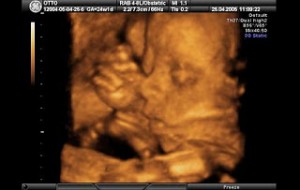

Hamileliğin (Gebeliğin) 35. Haftası Resim ve Video;

Bebeğin Boyutu: 43.7 cm, 1.9 kg